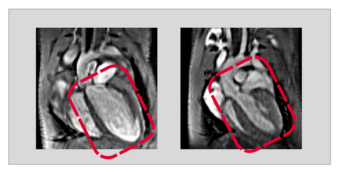

"Through a genetic intervention, we were able to specifically knock out USP5 in heart muscle cells of adult animals. If USP5 was then missing, a dilated cardiomyopathy developed in the following," reported Silke Kreher. Co-author Yvonne Eibach adds: "Using magnetic resonance imaging as a imaging method, we were able to impressively demonstrate that in these animals the entire heart was significantly enlarged and the pumping performance was severely restricted."